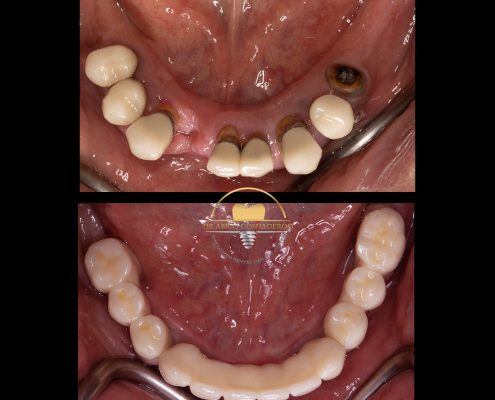

دکتر عباس گشاده رو متخصص ایمپلنت

دکتر عباس گشاده رو متخصص ایمپلنت در تهرانتلفن: 02126706197